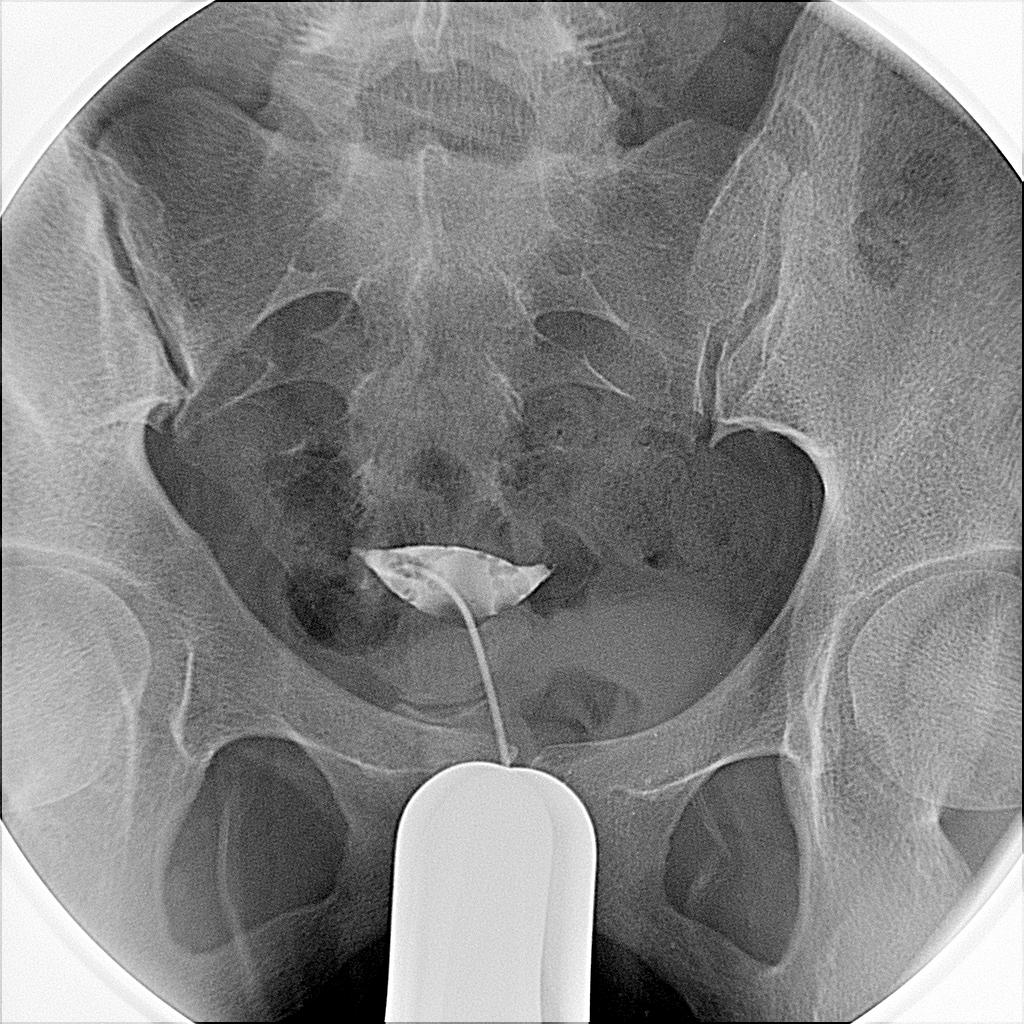

子宫输卵管造影提示双侧输卵管近端堵塞